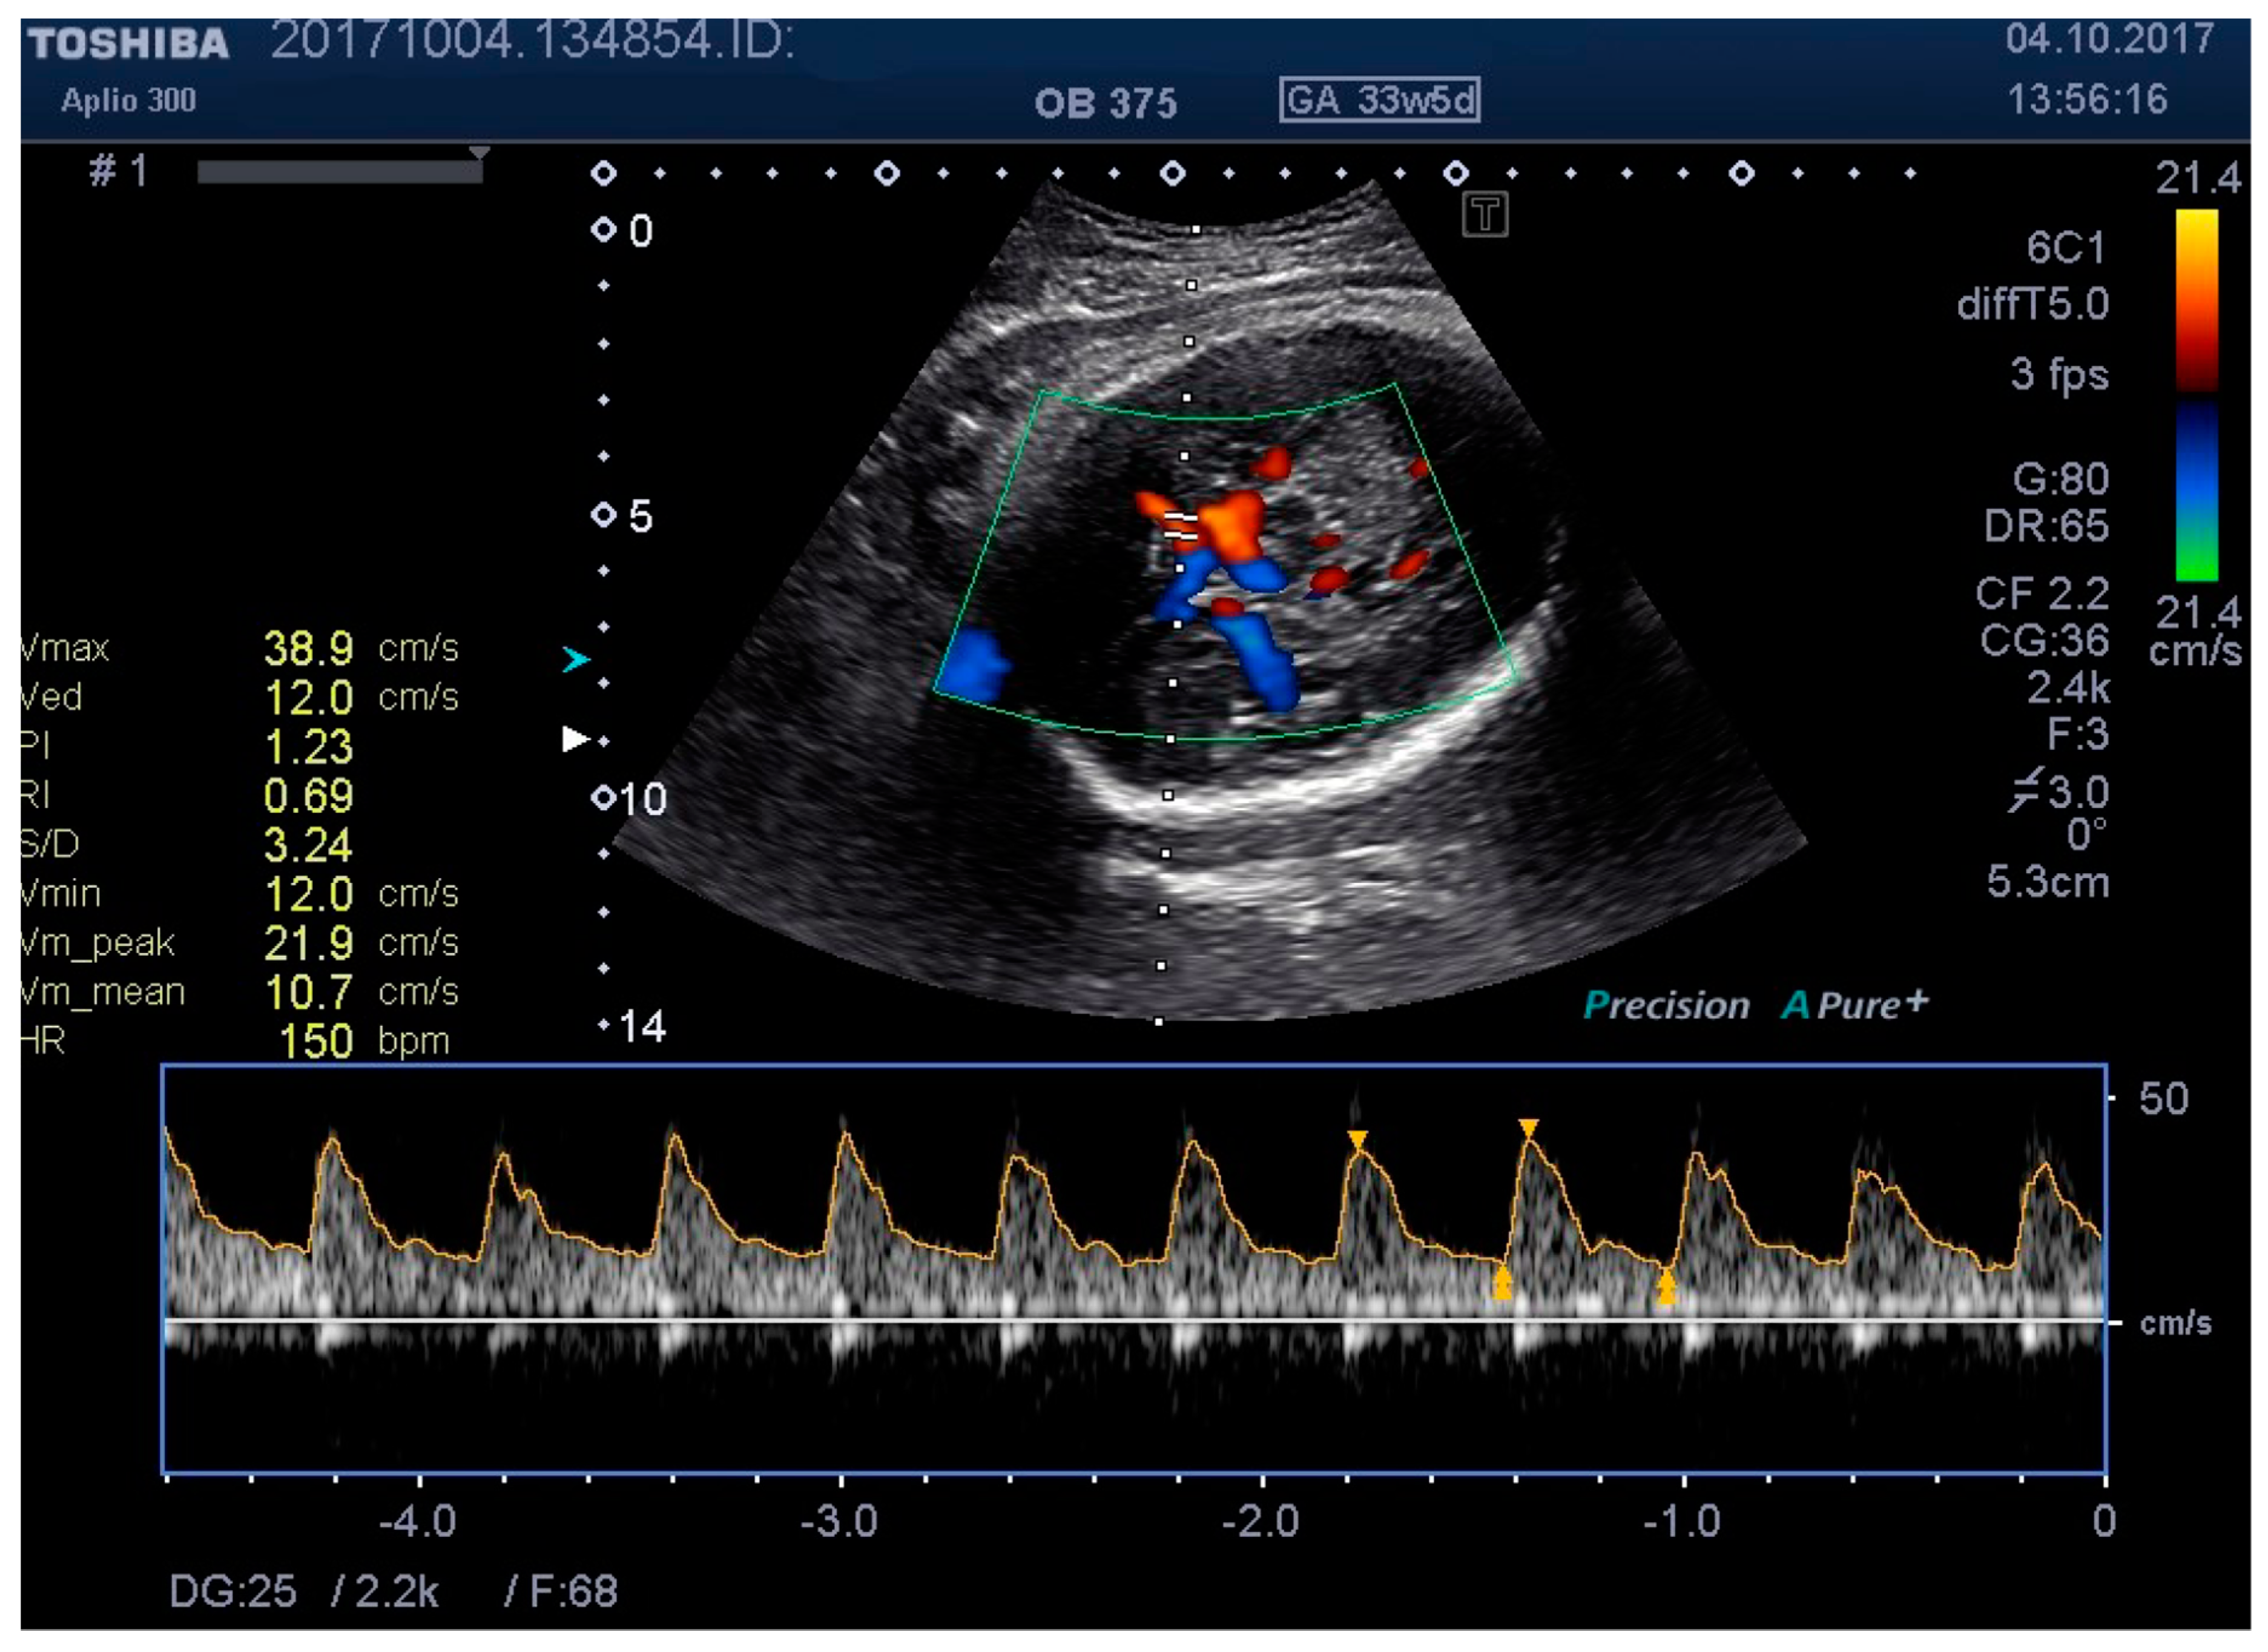

Figure 7. MCA Doppler spectrum with level 3 pressure.

Medicina 55 00410 g007

We examined the patients by transabdominal US, evaluating fetal lie and presentation, amniotic fluid index (AFI), area of placental insertion, and the abdominal wall thickness (AWT) including skin, subcutaneous tissue, and muscular wall. As a second step, we have evaluated the fetal cerebral vascularization, referring to the circle of Willis, with the help of color Doppler US, demonstrating the fetal MCA and recording the distance between the probe and the targeted vessel (e.g., MCA). By using pulsed Doppler examination, we recorded the flow velocity waveforms in the MCA, and measured the RI, PI, and PSV (using the highest point of the waveform). At the same time, we recorded, in a blinded manner, the applied pressure on to the maternal abdominal wall, considering this as a baseline pressure—needed for a proper evaluation of MCA. We then repeated the same measurements at two different higher pressure levels, while at the same time having a proper image of the targeted vessel. For the study methodology, we noted these pressure levels as level 2 and level 3.

Figure 1, Figure 2, Figure 3, Figure 4, Figure 5, Figure 6 and Figure 7 and Table 3 show the differences between MCA RI, PI, and PSV measured in the studied group, applying three different levels of abdominal pressure. As shown in the subsequent tables and figures, there are significant differences for the PI and RI levels with increase in abdominal pressure (median PI 1.46, 1.58, and 1.92, respectively; median RI 0.74, 0.78, and 0.85, respectively). Data are not following the normal distribution, thus, we used a Kruskal–Wallis test, which confirmed p < 0.05, for both PI and RI. At the same time, we found no significant differences for PSV in the studied group in relation to the increase in abdominal pressure (median PSV 39.56, 40.10, and 39.70 respectively). Data are not following the normal distribution, thus, we used a Kruskal–Wallis test, which showed p > 0.05.